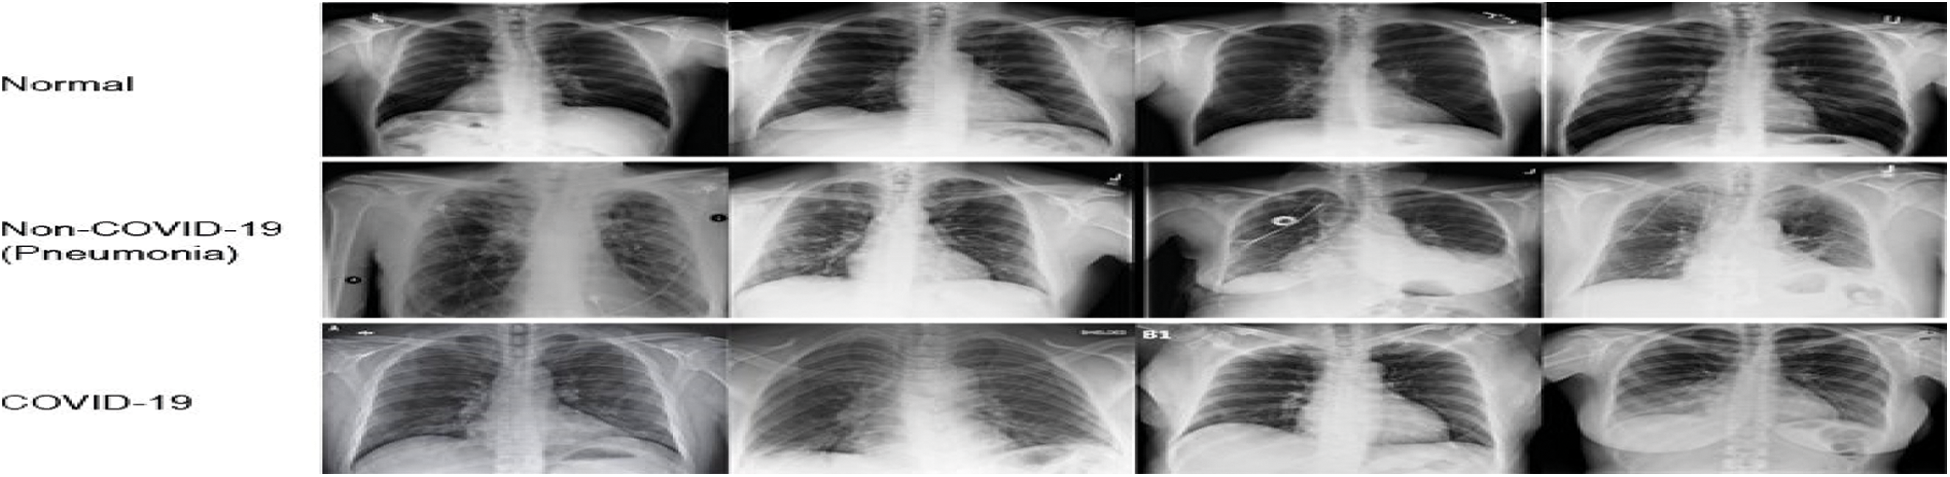

The classifiers results are obtained, in the classification of chest X-ray images using the MBWO-CNN model [29] dataset is discussed in this part. X-rays of the chest from COVID-19 and non-COVID individuals are included in the dataset [30]. COVID-19 has a total of 230 images, while the total number of image graphs in normal class is 29. Fig. 6, depicts some of the study’s test image graphs.

Figure 6: Normal, non- COVID-19 and COVID-19